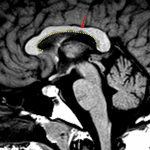

- Numerous supratentorial and infratentorial periventricular and juxtacortical T2/FLAIR hyperintense lesions including extensive lesions throughout the brainstem, many of which have associated T1 hypointensity

- Many lesions are oriented perpendicular to the ventricular margins

- Incomplete ring enhancement associated with lesions in the left cerebellar hemisphere, left parietal lobe, left frontal lobe, and right cingulate gyrus

- Multiple sclerosis with active demyelination

Extensive supratentorial and infratentorial white matter lesions with appearance and distribution consistent with the reported history of multiple sclerosis. Several lesions in the left cerebellar hemisphere, left frontal and parietal lobes, and right cingulate gyrus have associated enhancement concerning for active demyelination.